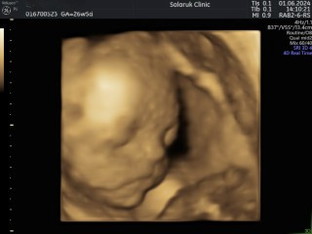

ซาวด์ 4 มิติ

ซาวด์น้องตอน 26w 5d แม่ไปซาวด์กันบ้างหรือยังคะ มาอวดน้องๆกันหน่อยค่ะ น่ารักจิ้มลิ้มกันบ้างมั้ย 🥰😍#ขอบคุณสำหรับคำคอมเม้นล่วงหน้าค่ะ